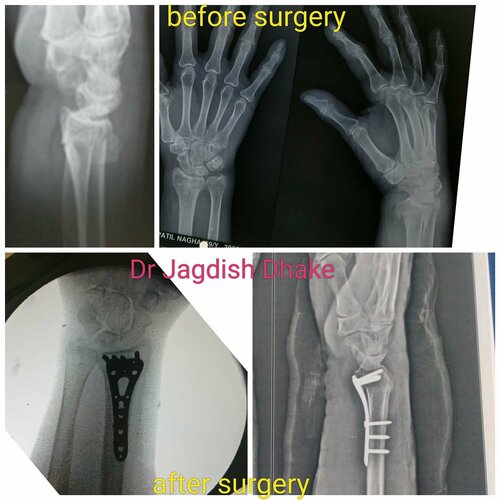

Hand Injury Case | Dr. Jagdish Dhake | Orthopedic Surgeon in Bibvewadi

Case 1: 26 year male, sport person, had fracture 5 the metacarpal (oblique displaced), operated with screw fixation, doing well after surgery. Case 2:...